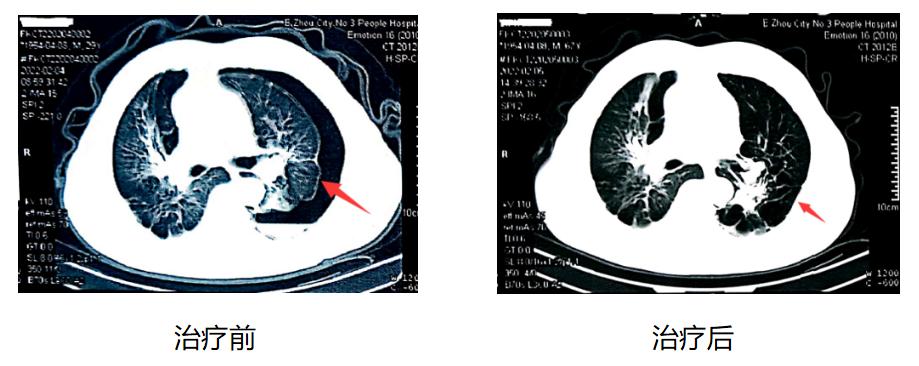

术后,复查胸部CT,提示原“左侧气胸”复查左肺中外带期内缘见肺压缩达10%,与前片比较,左侧肺气胸明显减少。影像前后对比图如下:

图1鉴别诊断